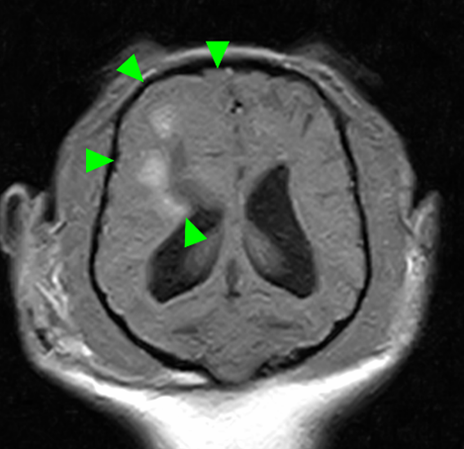

犬種 チワワ

年齢 7歳齢

体重 2.95kg

性別 去勢雄

運動失調(ふらつき、登れていた段差も登らなくなった)の主訴で来院。

初診から4か月後に重積発作で来院されたため、MRI検査を実施。

MRI検査:

右前頭葉にT2 強調画像/FLAIR 画像で高信号、T1 強調画像で一部低信号を示し、辺縁部で一部造影増強を示すびまん性の所見を認めた。この所見は、DWI 画像で高信号、ADC-map で大半が等~低信号を示していた。また左側前頭葉にも同様の信号所見を示す微小病変を認めた。

T2強調画像 横断像

FLAIR画像 横断像

DWI画像 横断像

ADC-map画像 横断像